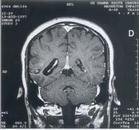

2.CT檢查 可見鈣化和單側腦萎縮。

斯特奇-韋伯綜合症CT掃描1.影像學檢查頭顱X線平片可顯示顱內鈣化影,呈腦回狀、線狀、樹枝狀、雙軌狀,其中與腦表面外形一致的雙軌狀是特徵性改變。顱內鈣化影可見於大腦各葉皮質,20歲以後的患者多見,發生率為50%~87.2%。多位於一側,雙側也有報導。CT平掃可見團塊狀混雜密度病灶,邊緣不清,可有鈣化影、局部腦萎縮;增強掃描可見異常血管強化影。MR成像上T1和T2加權均顯示低信號影,對鈣化的顯示不如CT掃描。數字減影血管造影(DSA)有助於腦部畸形血管的定性、定位。